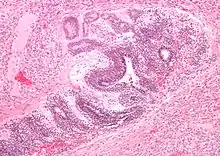

| Micrograph of the primitive neuroepithelium of an immature teratoma of the mediastinum. H&E stain. | |

The mediastinum has three main parts: the anterior mediastinum (front), the middle mediastinum, and the posterior mediastinum (back). Masses in the anterior portion of the mediastinum can include thymoma, lymphoma, pheochromocytoma, germ cell tumors including teratoma, thyroid tissue, and parathyroid lesions. Masses in this area are more likely to be malignant than those in other compartments.[2][3]